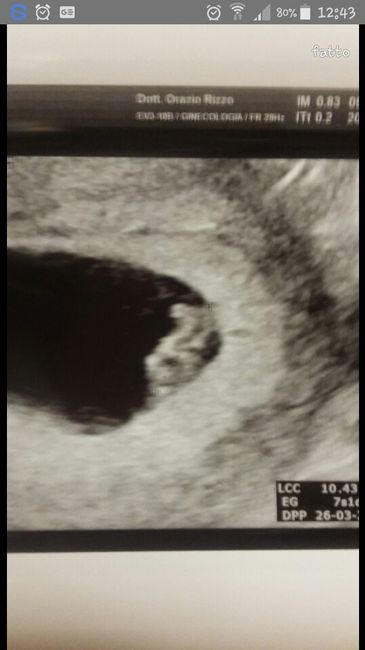

Ciao a tutte ragazze,ieri a 7 settimane +1 giorno ho fatto l'ecografia........anche se ancora non si capisce bene abbiamo visto il nostro/a piccolo/a......che emozione!!!! Non vedo l'ora che arrivi il 2 settembre per sentire il cuoricino battere.... ...